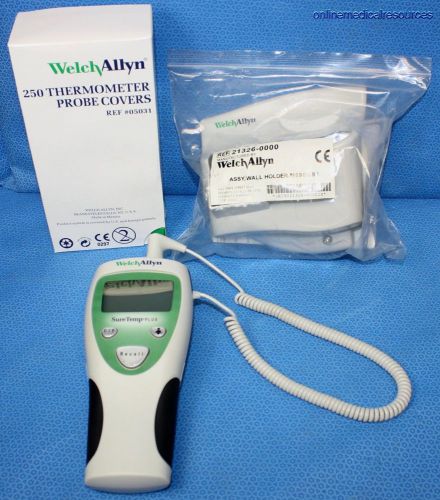

WELCH ALLYN SureTemp Plus 690 Digital Thermometer Oral Probe Wall Mount Covers